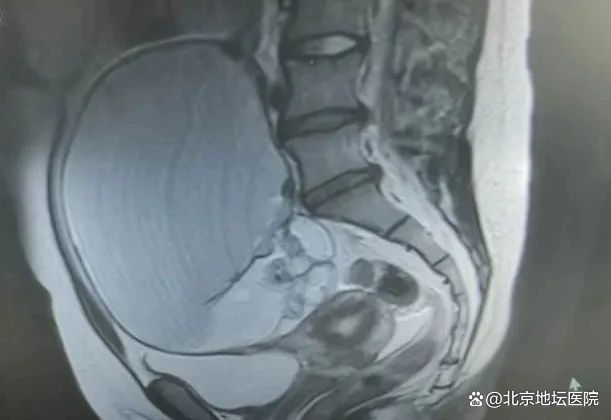

超声检查的结果让所有人倒吸一口冷气:一个直径20厘米的巨大盆腔肿物几乎填满了她的腹腔,这相当于在肚子里塞进了一个小西瓜!面临着肿瘤破裂、扭转、恶变等诸多风险,腹中的“不定时炸弹”危险异常!更令人揪心的是,多家医院给出的方案都是"开腹手术"——这意味着她的腹部将留下一条15厘米以上的疤痕。对于正值花季、热爱舞蹈的少女而言,这不仅是身体的创伤,更是心理的打击。

面对这个两难困境,妇产科团队反复评估、讨论,给出了一个颠覆传统的手术方案:经脐单孔腹腔镜手术。在患者和家属忐忑的期待中,手术团队仅通过肚脐处一个3厘米的切口,像拆解"俄罗斯套娃"般,将20厘米的肿瘤完整取出。术后病理证实为良性卵巢成熟性畸胎瘤,而当小雨看到自己几乎看不出痕迹的腹部时,终于露出了久违的笑容。